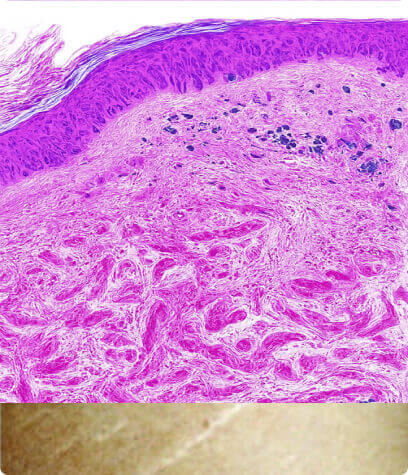

Dehnungsstreifen

Normale Haut

Glatt und elastisch, wobei intakte Kollagen- und Elastinfasern für Festigkeit und Struktur sorgen.

Striae Rubrae

Glatt und elastisch, wobei intakte Kollagen- und Elastinfasern für Festigkeit und Struktur sorgen.

Striae Albae

Reife weiße Dehnungsstreifen, bei denen die Umstrukturierung des Kollagens zu einer Ausdünnung und einem Verlust der Pigmentierung führt.

So funktioniert es

- Fördert den Abbau von geschädigtem Kollagen

- Es induziert die Proliferation von Keratinozyten, die Wachstumsfaktoren freisetzen, um die Kollagenablagerung durch Fibroblasten und die Elastinablagerung zu fördern.

- Moduliert die Expression mehrerer Gene in der Haut (vaskulärer endothelialer Wachstumsfaktor, Fibroblasten-Wachstumsfaktor, epidermaler Wachstumsfaktor, Kollagen Typ I und III), die die Umgestaltung der extrazellulären Matrix fördern.